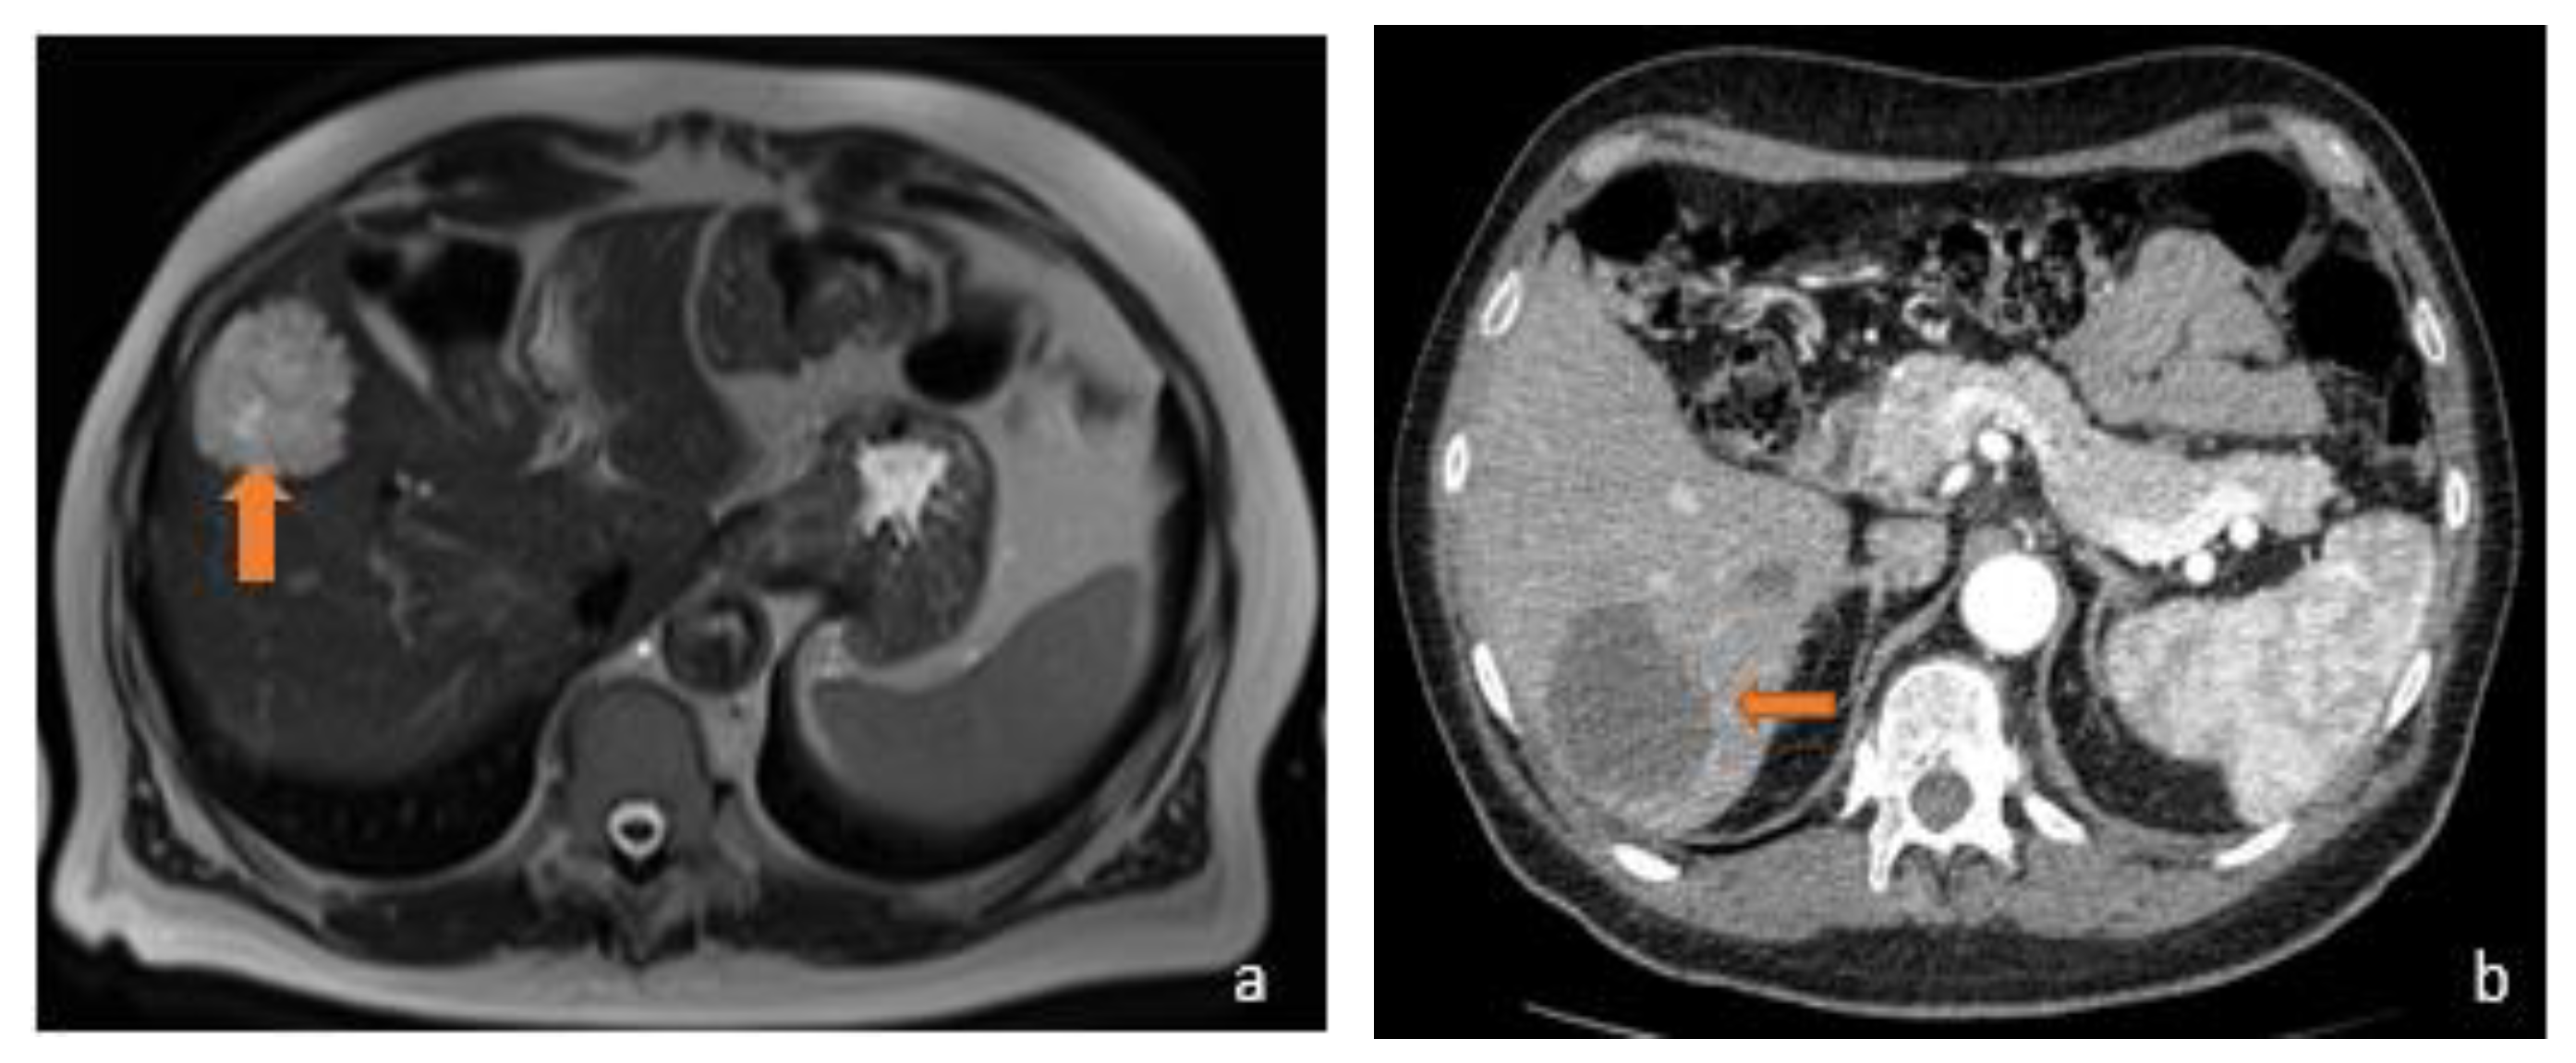

3.1. FLL Feature Characteristic

5.1. FLL Feature Characteristic

6. Benign MRI Features